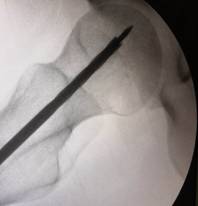

经过术前与麻师团队详尽的讨论及预案制定后,手术医师首先为吴先生实施双侧股骨头坏死髓芯减压,即打开一个像筷子大小的“隧道”孔后,再通过“隧道”将分离的血小板注射进吴先生骨头坏死区域。整个手术仅抽取了80毫升血液,耗时数十分钟,术后三天患者出院。

术中,为患者打通“隧道”,注入血小板